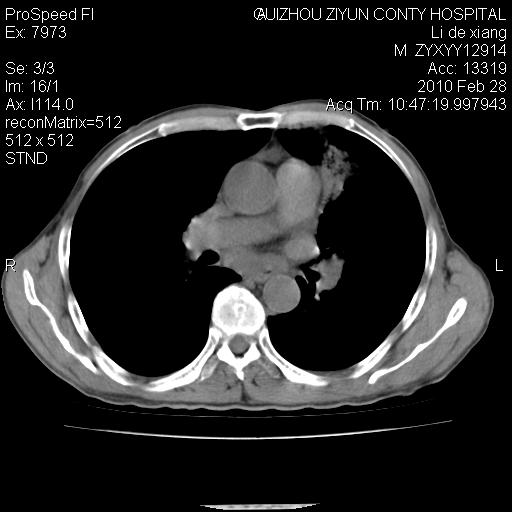

标题: CT24776:男 71Y 咳嗽咳痰胸痛两月,伴声音嘶哑。 [打印本页]

标题: CT24776:男 71Y 咳嗽咳痰胸痛两月,伴声音嘶哑。

左侧中央型肺癌伴左肺上叶阻塞性肺炎及节段性不张可能性大,建议纤支镜检查!

左侧中央型肺癌伴左肺上叶阻塞性肺炎及节段性不张可能性大,建议纤支镜检查!纵隔淋巴结转移.

左侧中央型肺癌伴左肺上叶阻塞性肺炎及纵隔淋巴结转移。

左肺门部肿块,伴左上肺斑块影,周边模糊,支持左肺中央型肺癌伴节段性不张及阻塞性肺炎,结合支气管镜检查。

左上叶支气管狭窄,阻塞性病变,肺门肿块,纵隔及肺门淋巴结增大,中央性肺癌

左肺中央型肺癌并阻塞性改变、纵膈 淋巴结转移

左侧中央型肺癌伴左肺上叶阻塞性肺炎及纵隔淋巴结转移

支持 左肺中央型肺癌伴左肺上叶阻塞性肺炎,纵隔淋巴结转移。